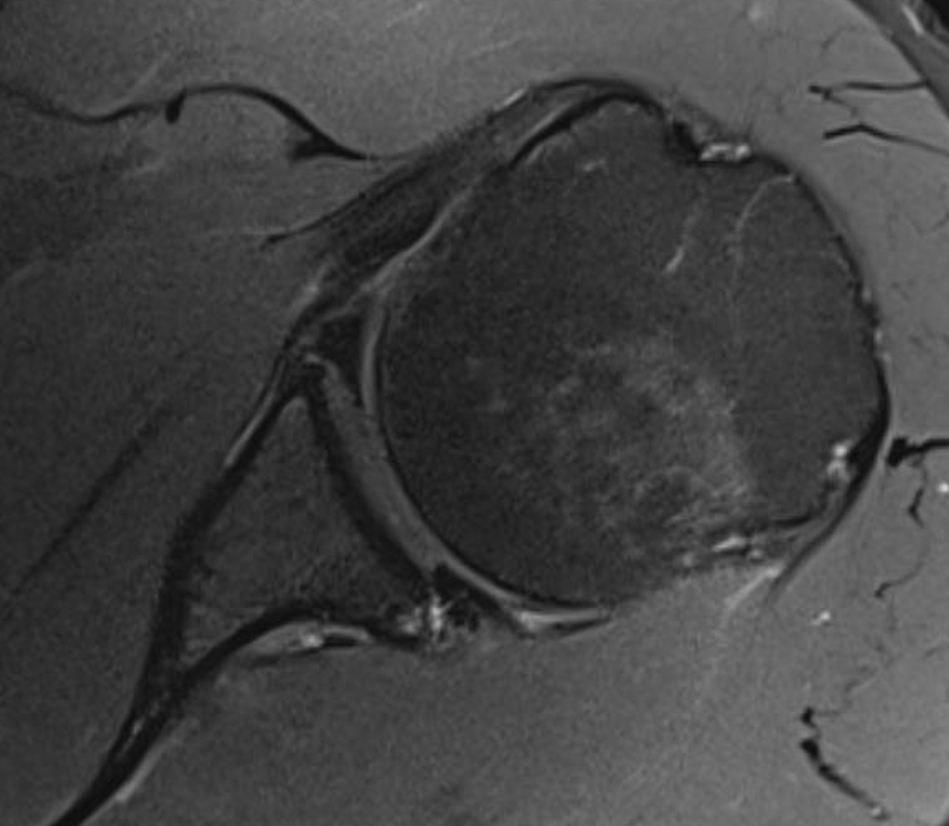

Kim lesion

- Kim lesion

- incomplete and concealed avulsion of the posteroinferior labrum

- superficial portion attached, deep portion detached

- labrum flat with loss of normal height resulting in retroversion of the chondrolabral glenoid